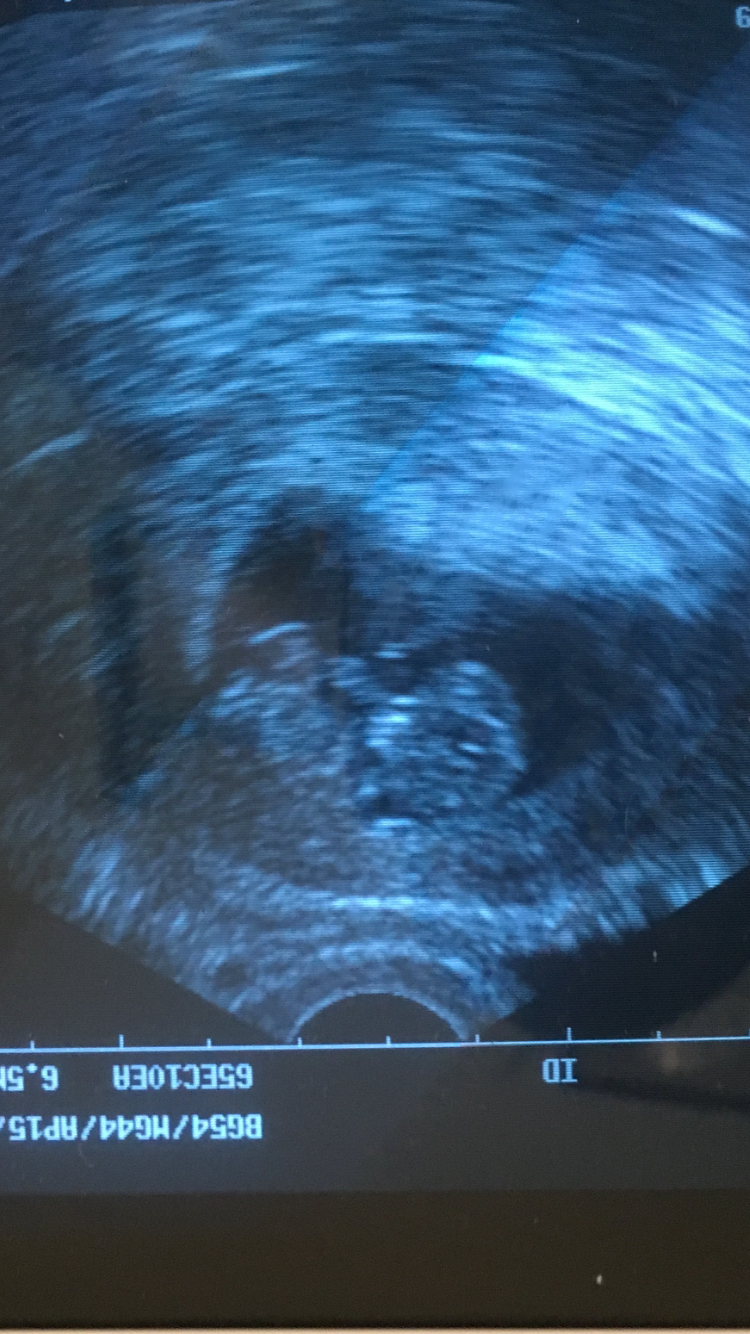

Re: Got to see the little guppy today! 10weeks!